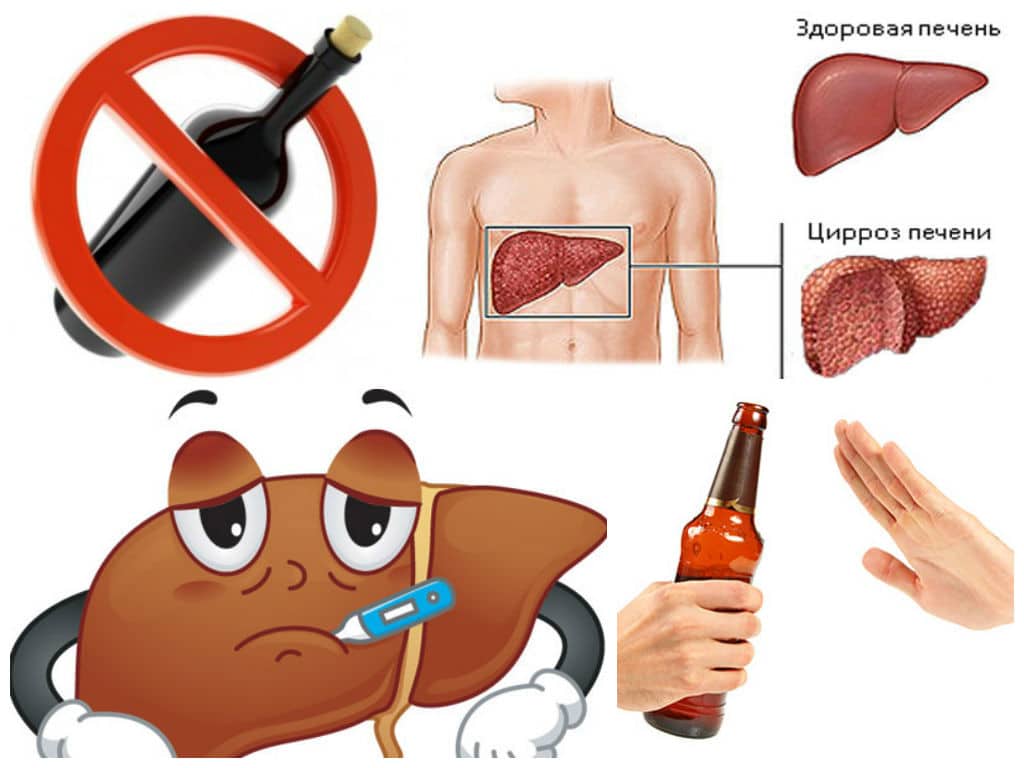

Признаки заболеваний печени: Важные симптомы и рекомендации